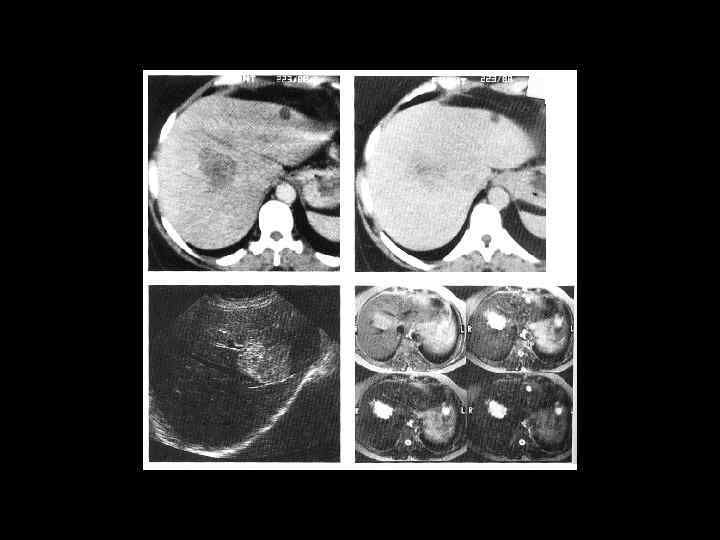

Та же пациентка